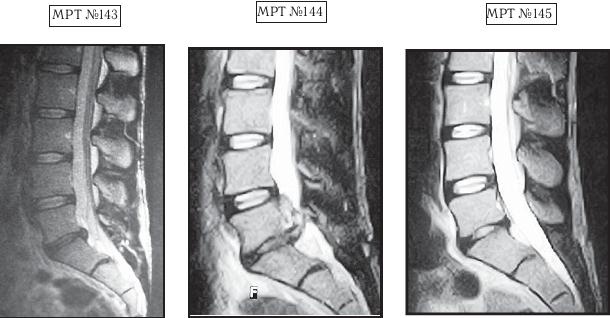

На МРТ №143 наблюдается состояние поясничного отдела позвоночника данного пациента до оперативного вмешательства: незначительных размеров грыжа межпозвонкового диска в сегменте LV-SI. Была проведена хирургическая операция межпозвонкового диска в сегменте LV-SI с целью профилактики возможных осложнений и дальнейшего прогрессирования грыжи. На МРТ №144 наблюдается состояние поясничного отдела позвоночника того же пациента после хирургического вмешательства: рецидив грыжи (но уже со значительным секвестром) межпозвонкового диска в сегменте LV-SI, стеноз позвоночного канала и, естественно, соответствующие осложнения, вызванные такой ситуацией (во избежание которых собственно и была проведена операция). На МРТ №145 наблюдается состояние поясничного отдела позвоночника того же пациента после одного курса лечения методом вертеброревитологии: отсутствие секвестрированной грыжи, стеноза позвоночного канала. |